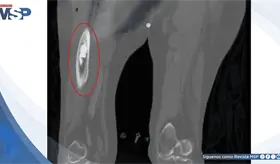

El VIH debilitó gravemente el sistema inmunológico del paciente (CD4 162), permitiendo que una bacteria poco común como Rhodococcus causara un absceso pulmonar severo que simuló tuberculosis y no respondió al tratamiento habitual.